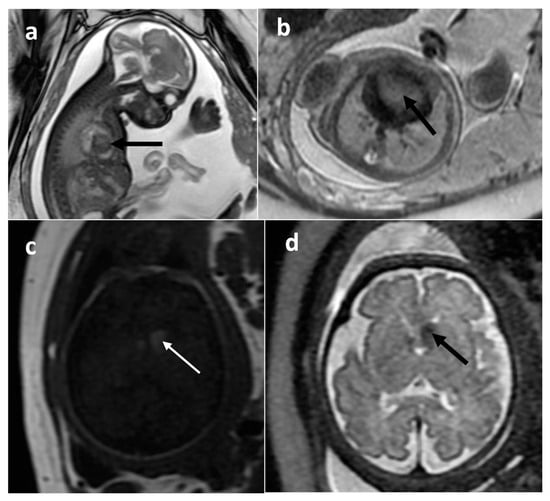

| Brain stem glioma | brain stem | 2 | [12.5–18.41] | no (1266–1430) | microcystic/solid | 1/2 | 0/1 |

| Desmoplastic infantile astrocytoma (DIA) | right middle cranial fossa | 1 | 52.7 | N/A | Solid | N/A | N/A |

| Choroid plexus carcinoma | left cerebral hemisphere | 1 | 182 | N/A | Mixed | N/A | N/A |

| Glioblastoma | right cerebral hemisphere | 1 | 140 | yes (492) | Mixed | yes | N/A |